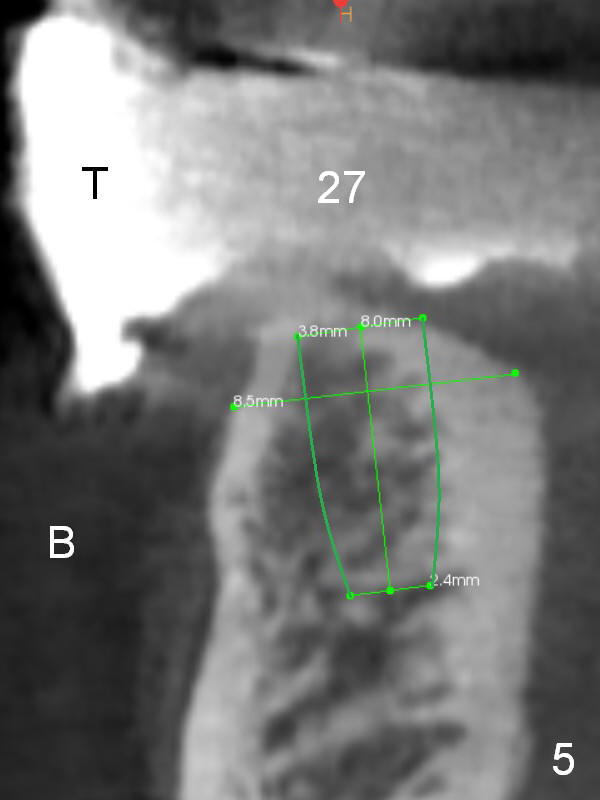

The patient wants to change unstable complete dentures to fixed ones. Because the problem of pain is associated with the lower left (Fig.1 the left Inferior Alveolar Nerve is more superficial), the lower arch will be reconstructed first. Totally 6 implants will be placed for bridges/crowns. Due to time constraint, four implants are placed at the 1st stage (#21, 22, 27 and 28 (Fig.4,5,8,9)); the lower denture will be retained immediately by ball abutments and soft relined. Two to three months later, two more implants will be placed (at #31 and 20, Fig.2,10). Note severe atrophy of the crest at #18 and 19 (Fig.11 and 12). If primary stability is achieved, a fixed immediate provisional will be fabricated.

In contrast to the upper arch, the bone density in the lower arch is high. The challenge is bone height. Short implants will be used (6 mm for #31 (Fig.2) and 8 mm for the majority of the others (at premolar and canine sites). If needed, extra implants will be placed at incisor sites (Fig.6,7 (implant can be longer)) and at #29 (Fig.3) . If a site is too small for a 3.8 mm 2-piece implant, a 1-piece one may be placed.